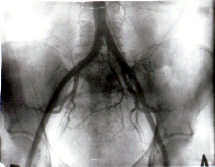

При изменении направления микроциркуляции в злокачественных

опухолях различного гистогенеза наблюдаются различные эффекты

в зависимости от показателей интенсивности фильтрации. При ее

10-кратном возрастании опухолевая ткань подвергается трансформации

в кость (Рис. 1, 2, 3, 4). При 20-крат-ном - опухолевые

клетки подвергаются некробиозу, в ранее аваскулярных зонах возникают

капиллярные сети, опухоль изолируется от окружающих тканей, она

сокращается в размерах более чем на 50% от исходных, исчезают

осложнения: кровотечения, боли и др.